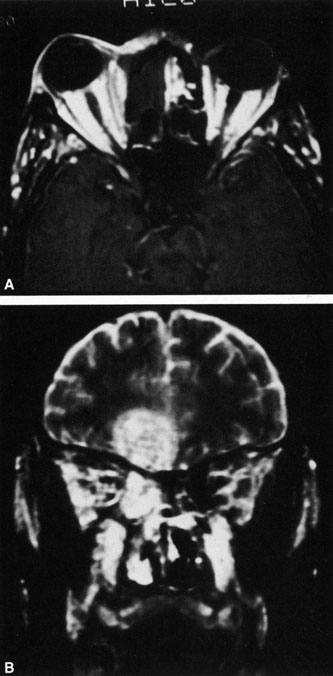

Rhinocerebral mucormycosis originates as a rhinitis, parapharyngitis, or sinusitis, and spreads by invasion of blood vessel walls, causing a necrotizing vasculitis with thrombosis of the vascular lumina and resultant infarction. The patient typically presents with unilateral orbital apex syndrome, including severe pain, visual loss, total ophthalmoplegia, corneal anesthesia, and multiple cranial nerve palsies.127 Orbital cellulitis presenting with early visual loss is one of the hallmarks of mucormycosis.72 Gangrene may occur of external periorbital tissues as well as of the hard palate and nose, and eschar-like crusting may be observed within the nose or on the hard palate (Fig. 23). Obstruction of the central retinal artery, ciliary arteries, and choroidal circulation can also be seen.124,125 Brain damage may occur because of spread of infection or infarction or occlusion of affected intracranial vessels.72

Fig. 23. Mucormycosis of the right ethmoidal sinus, with right orbital subperiosteal abscess formation. A. T1-weighted axial image. B. T2-weighted image. Note brain abscess.

CT shows sinusitis with or without bone destruction and is indistinguishable from other causes of orbital cellulitis.128 MRI may show carotid narrowing, occlusion, and absent flow in the superior ophthalmic vein (Fig. 24).72